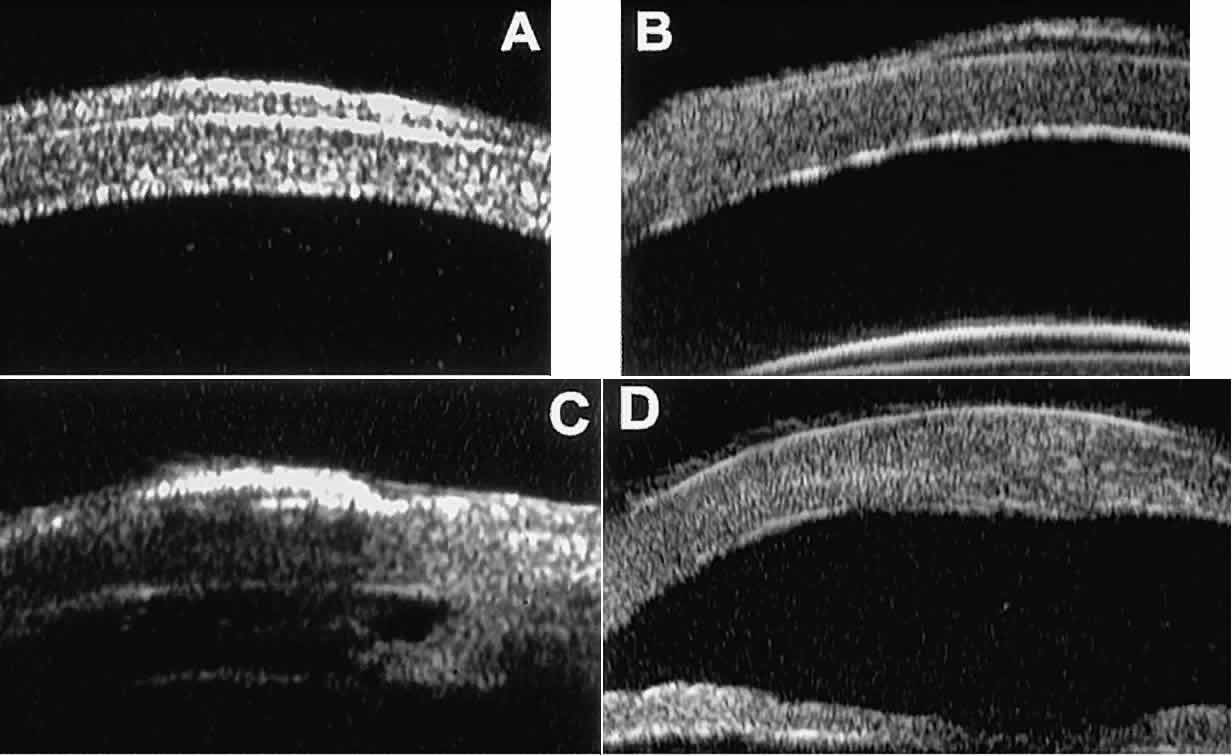

In open-angle glaucoma, UBM can be used to measure the anterior chamber angle in degrees, to assess the configuration of the peripheral iris, and to evaluate the trabecular meshwork (Fig. 9).2,4 The angle configuration can be graded and compared with gonioscopic findings. In certain patients with open-angle glaucoma, UBM can provide information that may be of some diagnostic value (Fig. 10). For example, in pigment dispersion syndrome (see Fig. 10A),6 UBM typically reveals posterior bowing of the peripheral iris (“q” configuration of peripheral iris by Spaeth classification5). In plateau iris syndrome (see Fig. 10B),7 UBM usually reveals abnormally steep anterior angulation of the peripheral iris (“s”configuration of peripheral iris by Spaeth classification5), insertion of the iris from the anterior ciliary body, and retroiridic projection of the ciliary processes. In eyes with peripheral anterior synechiae (see Fig. 10C and D), UBM can reveal the extent of iridocorneal adhesion even if the cornea is hazy or opaque.

Fig. 9. Angle configuration in eyes with open-angle glaucoma. A. Wide open angle with flat iris plane (D40r configuration by Spaeth gonioscopic grading system). B. Moderately wide angle with anteriorly bowed iris plane (C30r by Spaeth gonioscopic grading system).

Fig. 10. UBM features of special glaucoma cases. A. Pigment dispersion syndrome with posterior bowing of peripheral iris (“q” configuration by Spaeth gonioscopic grading system). B. Plateau iris syndrome with origin of iris from anterior surface of ciliary processes behind peripheral iris, slitlike narrowing of peripheral angle, and abrupt transition from steep peripheral iris to flat iris midzone. C. Broad peripheral anterior synechia with posterior bowing of nonadherent iris. D. Peripheral anterior synechia with aqueous-filled slit between site of iridocorneal adhesion and iris root after cataract extraction with implantation of posterior-chamber IOL.

In eyes with a narrow angle, UBM shows the extent of angle closure, reveals the depth of the anterior and posterior chambers, and identifies pathologic processes pushing the lens and iris forward (Fig. 11).2–4,8 UBM has been able to differentiate between primary angle closure (i.e., cases of angle closure without additional pathology responsible for the anterior lens-iris displacement [see Fig. 11A] and secondary angle closure due to processes such as lens swelling and dislocation (see Fig. 11B), massive hemorrhagic retinal detachment pushing the lens and iris anteriorly (see Fig. 11C), and multiple neuroepithelial cysts of the iridociliary sulcus (see Fig. 11D).

Fig. 11. Angle configuration in eyes with angle-closure glaucoma. A. Primary angle-closure glaucoma with anterior displacement of lens and iris. B. Angle closure secondary to swollen, cataractous lens (phakomorphic angle closure). C. Angle closure secondary to massive hemorrhagic retinal detachment; the subretinal blood is evident in the lower right corner of the photograph. D. Angle closure secondary to multiple peripheral iris cysts.